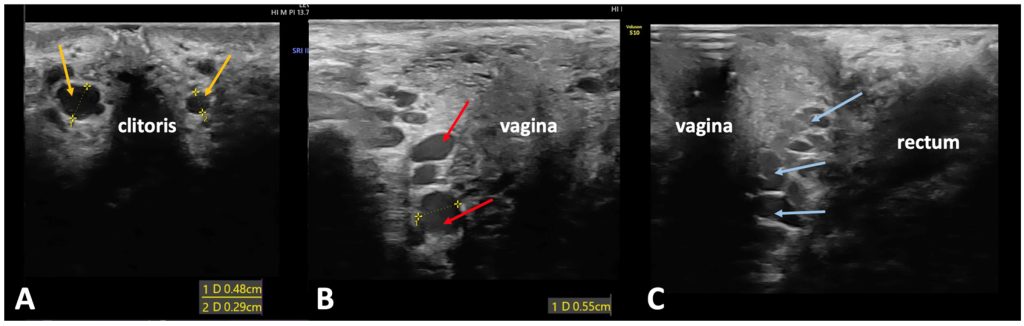

Вульварные точки выхода связаны с внутренней половой веной, которая находится в пределах полового канала. Эта вена имеет притоки, такие как глубокие дорсальные вены клитора, вены луковицы преддверия влагалища и промежностные вены.. Исходя из особенностей анатомии, особое внимание уделяется трём основным местам выхода из таза (рис. 1):

Рисунок 1. А — места выхода около клитора справа и слева. B — промежуточная точка выхода в области малых половых губ, расположенная посередине больших половых губ. C — точка выхода вблизи промежности, находящаяся в задней трети больших половых губ.